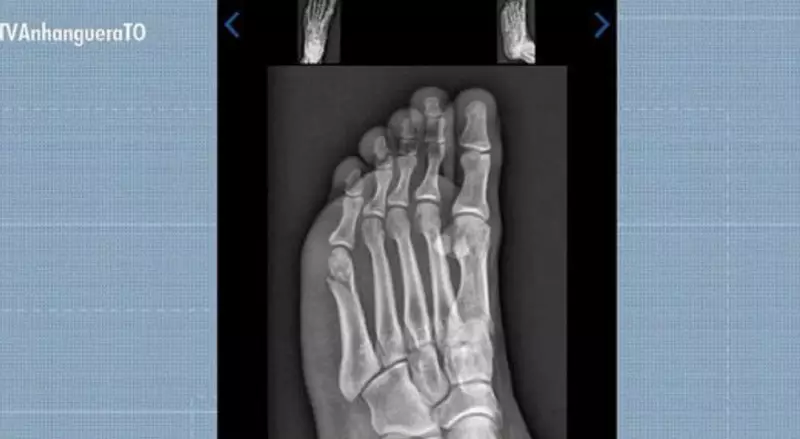

Em uma impressionante demonstração de determinação, o concurseiro Gabriel Santos Rodrigues, de 22 anos, natural de Gurupi, no sul do Tocantins, conseguiu ser aprovado no Teste de Aptidão Física da Polícia Militar mesmo com uma fratura no pé. O acidente ocorreu exatamente 30 dias antes da prova, quando o jovem caía do telhado de sua própria casa enquanto realizava a troca da boia da caixa d'água.